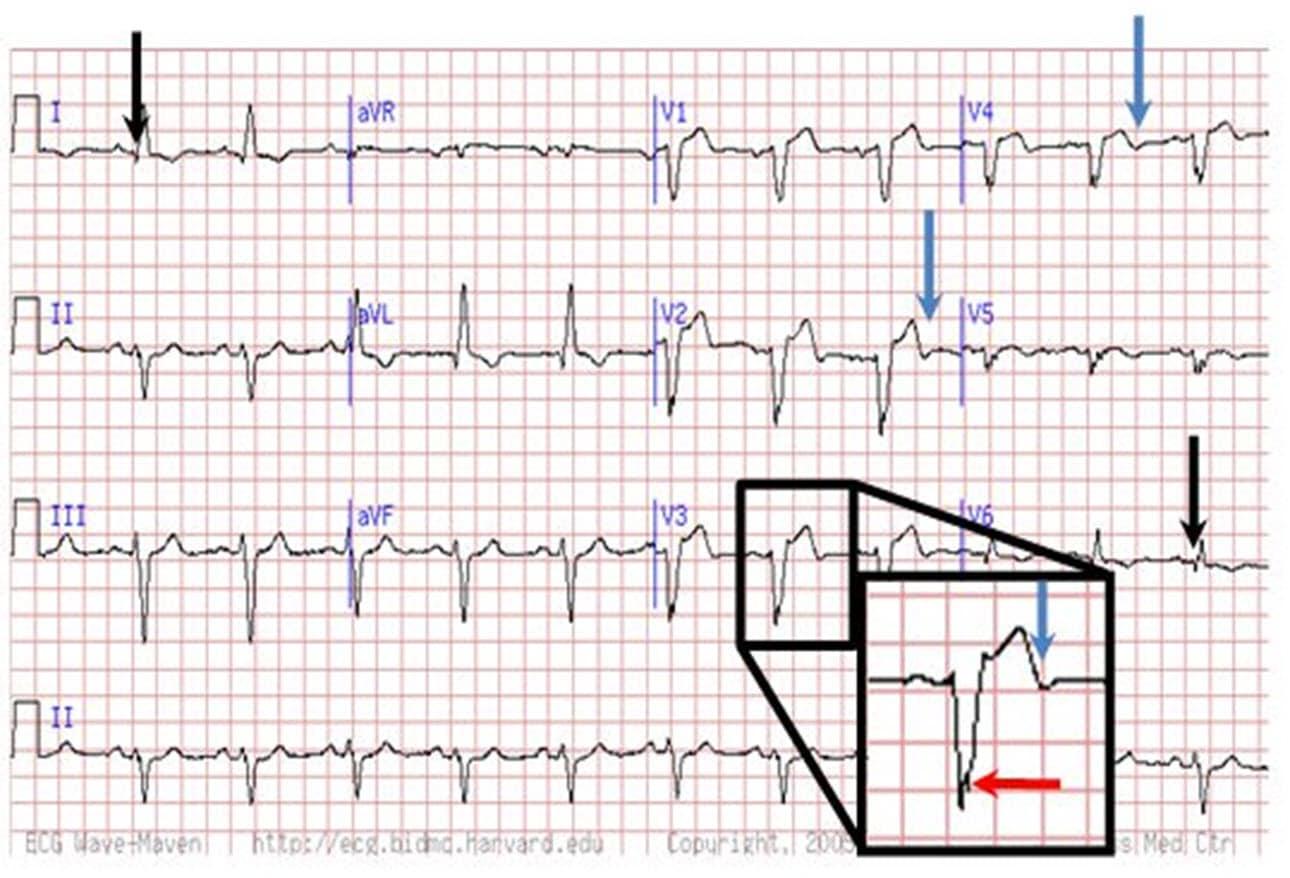

Dr. Smith's ECG Blog Chest Pain and Qwaves in V1 and V2. Is there

Dr. Smith's ECG Blog Chest Pain and Qwaves in V1 and V2. Is there Isolated Q Wave In Lead Iii A myocardial infarction can be thought of as an elecrical 'hole'. These findings highlight the need for. Small q waves are normal in most leads; Table 2 shows the prevalence of minor isolated q waves in any of the 3 ecg lead groups (anterior, lateral, and inferior) and in each lead group. By definition, a q wave on the electrocardiogram. Isolated Q Wave In Lead Iii.